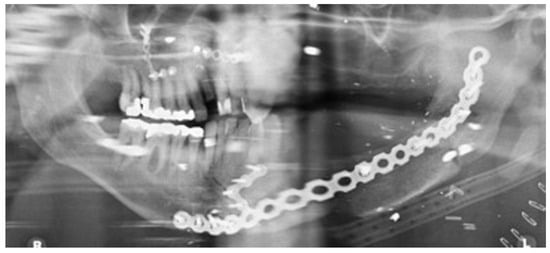

Figure 11.

Orthopantomography(OPT) showing free bone graft placed in segmental defect.

Staged reconstruction was defined as when the reconstruction with the free bone graft was performed as a secondary procedure. This secondary procedure was only performed when the oral mucosa had healed intraorally, sealing the mouth from the defect and the neck. A loadbearing locking mandibular plate was used to maintain the three-dimensional position of the bone and thus the occlusion (see Figure 1, Figure 2, Figure 3, Figure 4, Figure 5, Figure 6, Figure 7, Figure 8, Figure 9, Figure 10 and Figure 11).

All the reconstructions in our study were staged. The average length of the free bone grafts was 6.7 cm (range: 6.0–7.1 cm) and the average height of the free bone grafts was 2.3 cm (range: 1.0–3.2 cm). The follow-up period was between 6 and 108 months (average 30 months). Twelve patients had no complications at the recipient site and two patients had minor wound breakdown extraorally, which resolved with antibiotics. One bone graft was lost due to infection. In Birmingham, two patients had been dentally rehabilitated with implants. Another four patients have been scanned and are awaiting dental implant placement. No patient in Florida was dentally rehabilitated with dental implants.